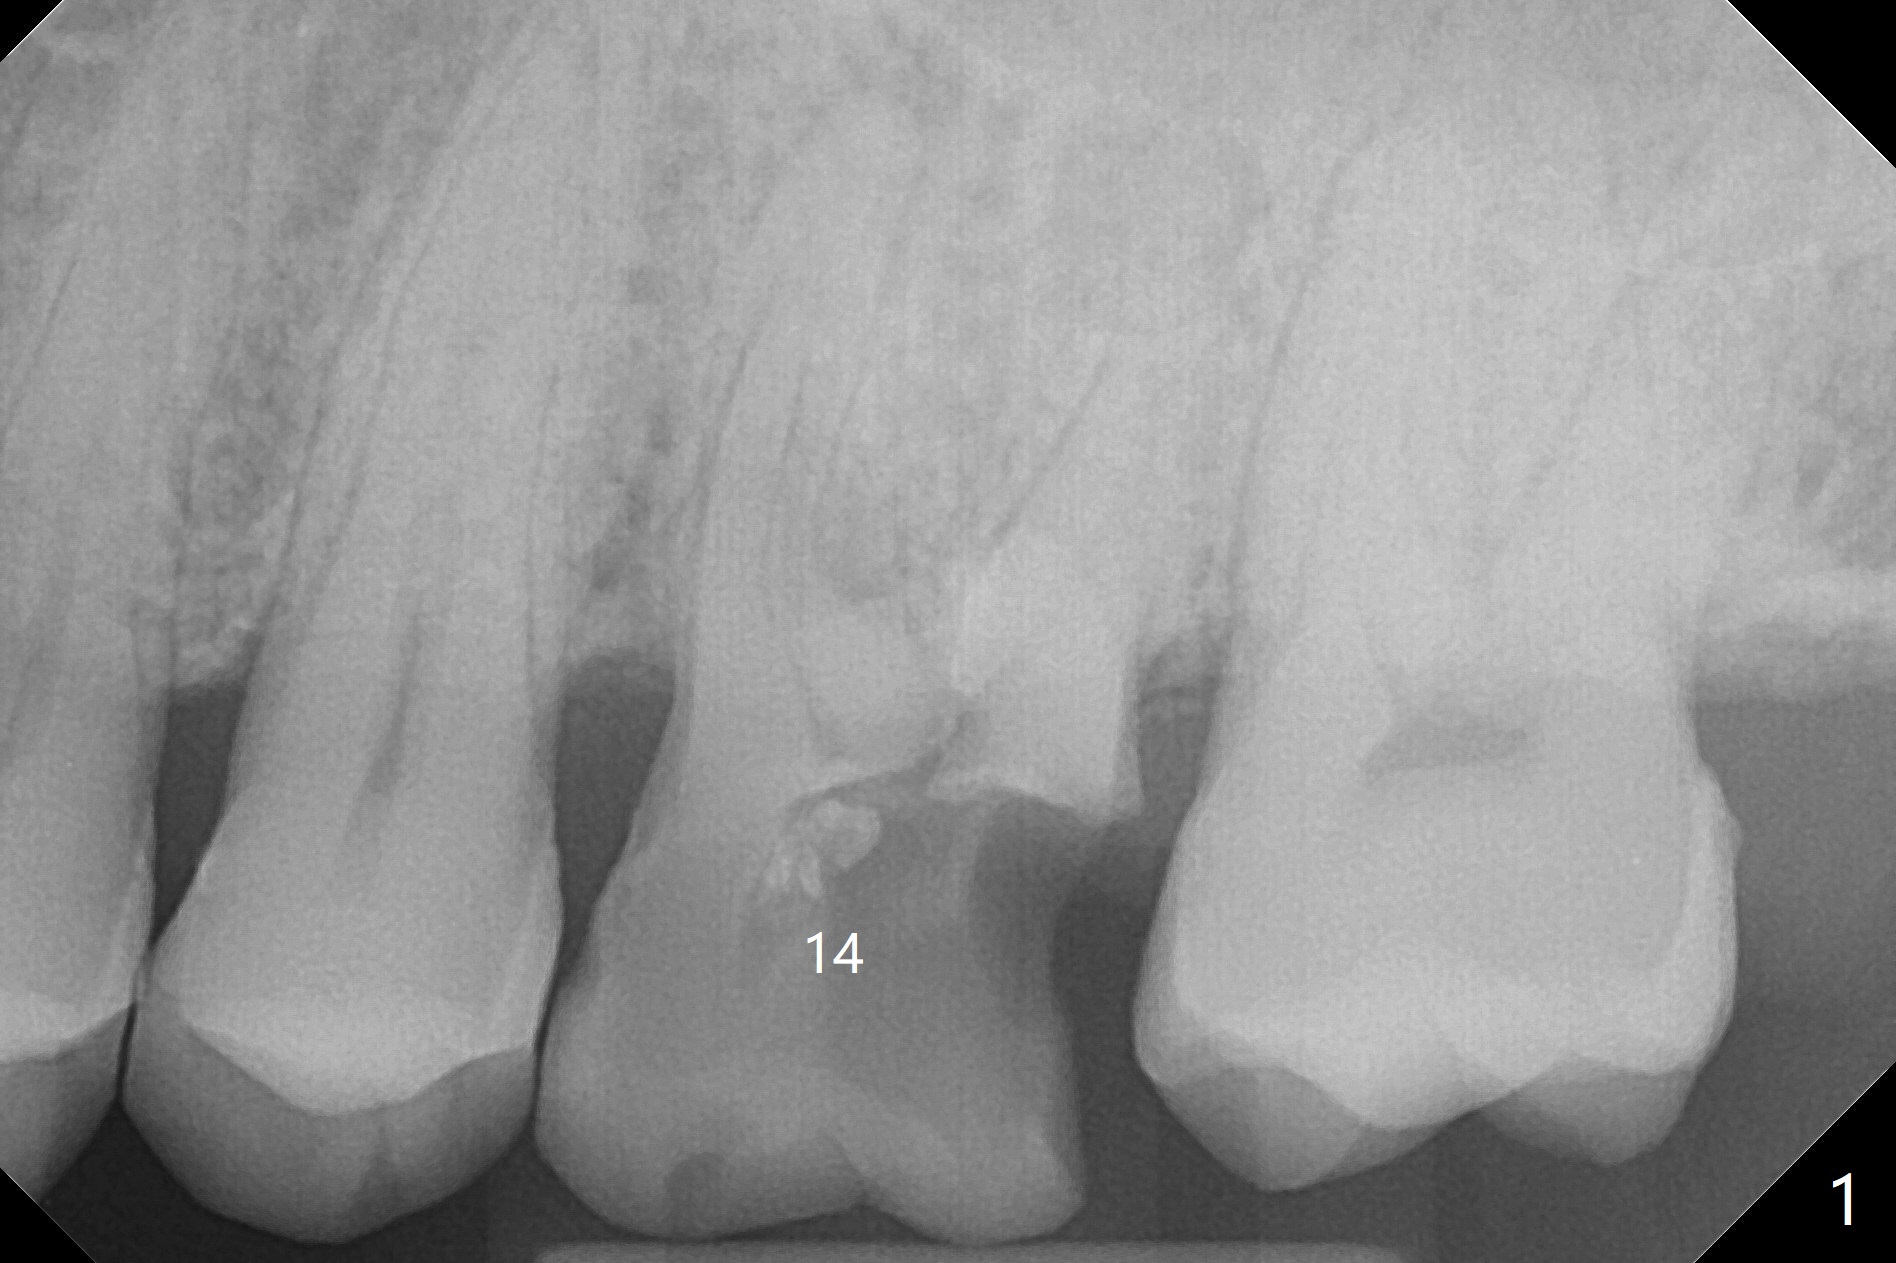

A 48-year-old man returns for implant at #14 after endo consult (Fig.1). The tooth appears to have fractured subgingival palatal (Fig.2,3 P). The furca is thin (Fig.3 *). A 5x10 mm implant will be placed slightly away palatal because of bone loss (Fig.4). Since the mesiobuccal (Fig.5 MB) and distobuccal (DB) sockets are close to the osteotomy (green), gauze with 1:50,000 Epinephrine (to reduce hemorrhage during sinus lift) will be placed away from the osteotomy (Fig.6 white area). In fact socket shield is conducted palatal.